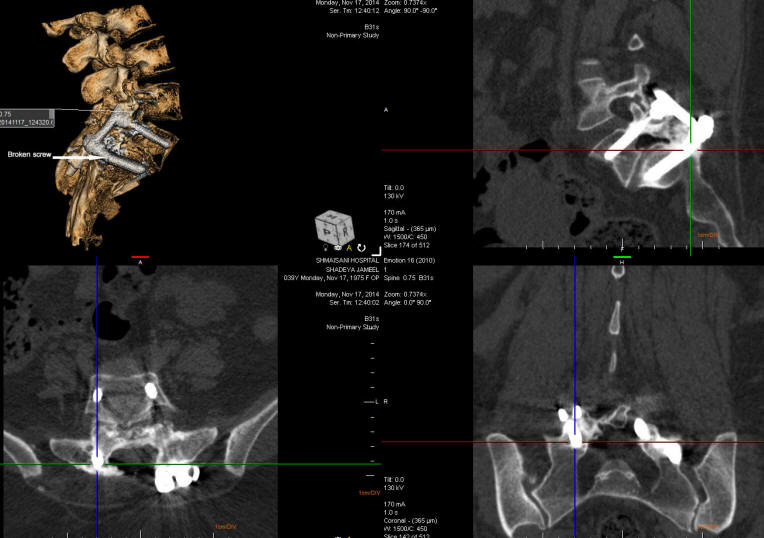

21-DECEMBER-2014  SHADYA JAMEEL AL-QAZAA  39 YEARS  RESIDUAL AFTER FIXATION OF L5-S1 WITH AGONIZING RIGHT SCIATICA.

The patient was operated elsewhere 2004 for spondylolisthesis L5-S1. The patient improved slightly and the last 4 months got agonizing right sciatica. MRI lumbar spine done 12-November-2014, not informative. Micturition problems for 2 months.

On examination, the patient is limping with exaggerated scoliotic stance in pain with SLRS 20 degrees with pain in the right and 60 degrees with pain in the left. There is weak dorsi and planterflexion right foot -3/5 with hypalgesia below the right knee.

The patient was sent for investigations. MRI dorsal spine was normal and the lumbar ruling out the presence of discitis of escalation of other disci. LSS-X-rays dynamic showing loosening of the right construct with broken right lower screw. CT-scan with ORS Visual software showing the broken right lower screw ( See the picture below).

The four screws were exposed and the right transpedicular screws were removed. 2 polyaxial Medtronic Legacy CDH screws  6.5x45 mm were inserted from the right. The broken tip of the previous screw was left in place. In the left side the screws were acceptable and there was a heeled bone graft. In the right side there was no bone graft. Using Inomed technology, the roots were responding to 2-4 mA DNS stimulation and the right inserted rods did not respond even to 15 mA DNS stimulation. A 5.5 mm bended rod and cross connector were added to obtain stability of the area with bone graft applied lateral to the right rod. Routine closure of the wound.

Smooth postoperative recovery. The power of the right foot became better.

The broken screw made the right side of the spinal column unstable, which caused the sciatica.  Replacement of the right screws with cross connector must resolve the problem.

ORS Visual reconstruction showing the right lower screw broken.